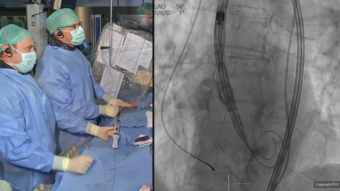

Transcatheter Tr Repair Tops Medical Management Mdedge Cardiology

Dr C Michael Gibson Talks With Dr Maurizio Taramasso About A Propensity Score Matched Analysis Of Transcatheter Tricuspid Tctmd Com

Transcatheter Versus Medical Treatment Of Symptomatic Severe Tricuspid Regurgitation A Propensity Score Matched Analysis Maurizio Taramasso Md Phd From Ppt Download

Transcatheter Options Best For Tricuspid Regurgitation In Matched Registry Analysis Tctmd Com